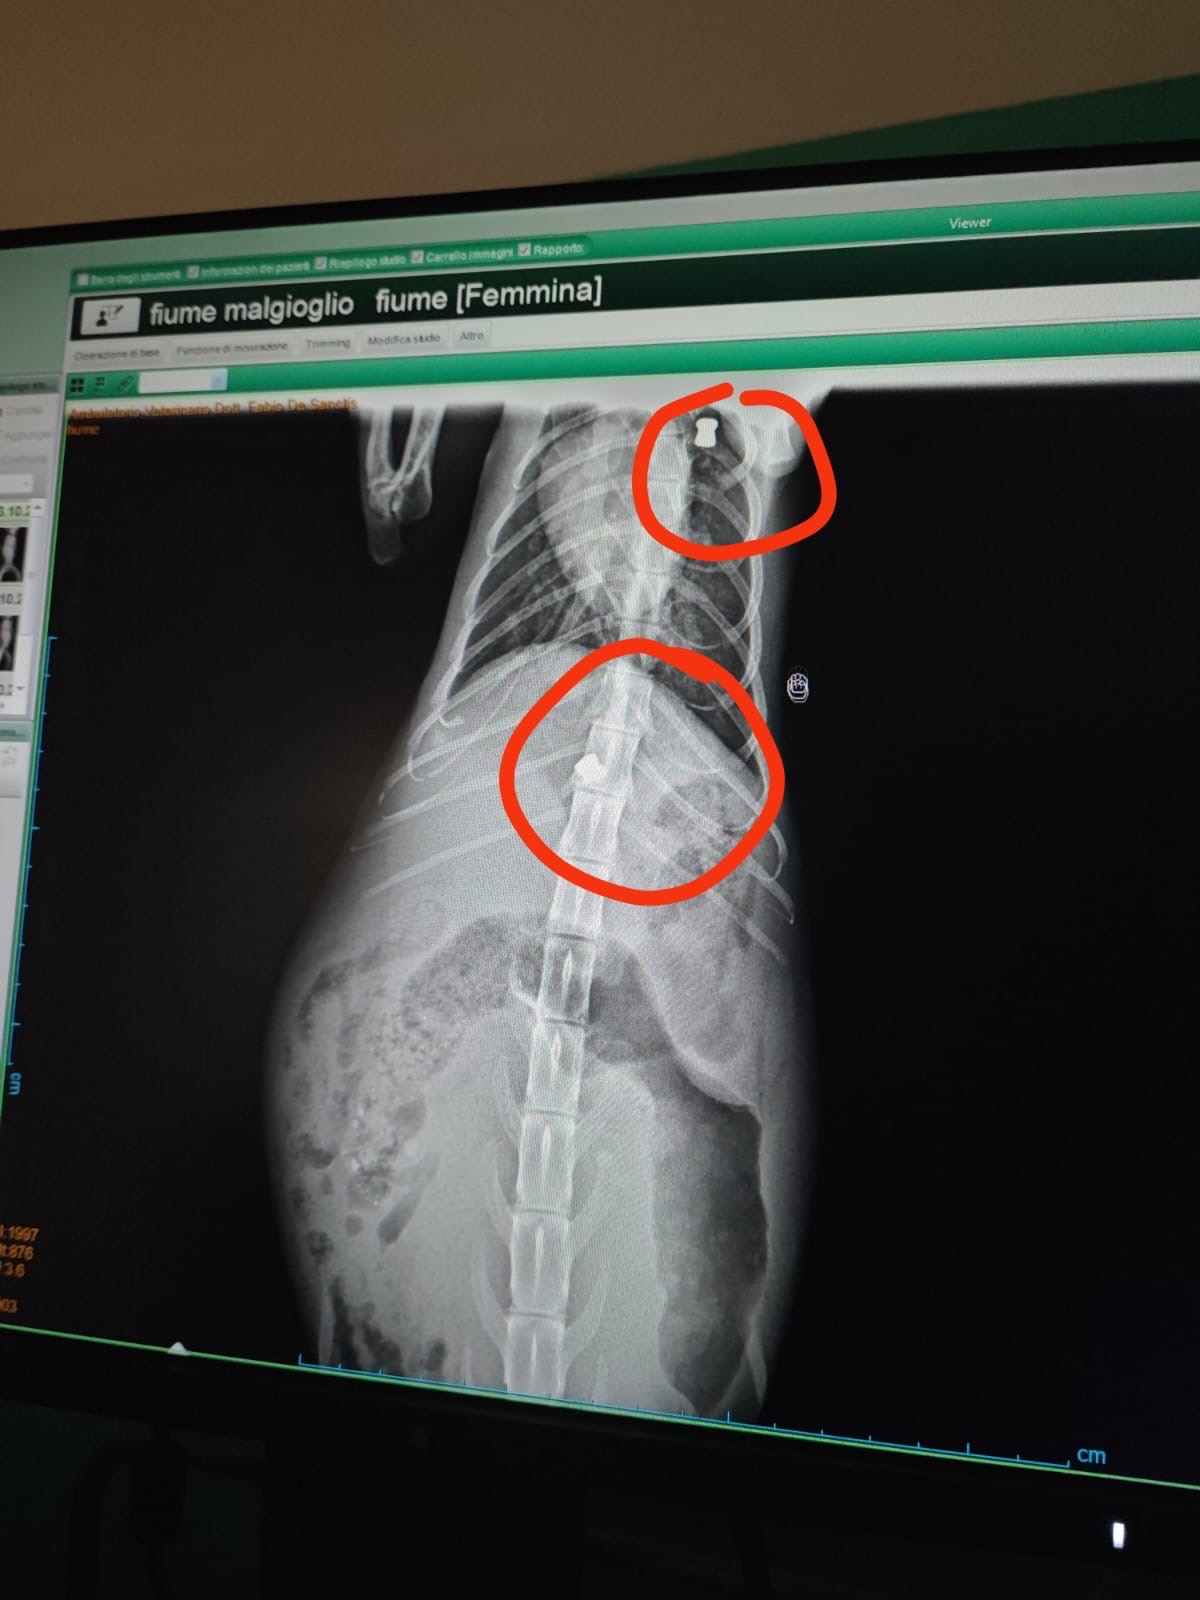

le hanno sparato con un fucile a piombini.

Un pallino si è conficcato nella colonna vertebrale causandole la paralisi delle zampe posteriori, mentre l’altro si è fermato a meno di 1cm dal cuore..